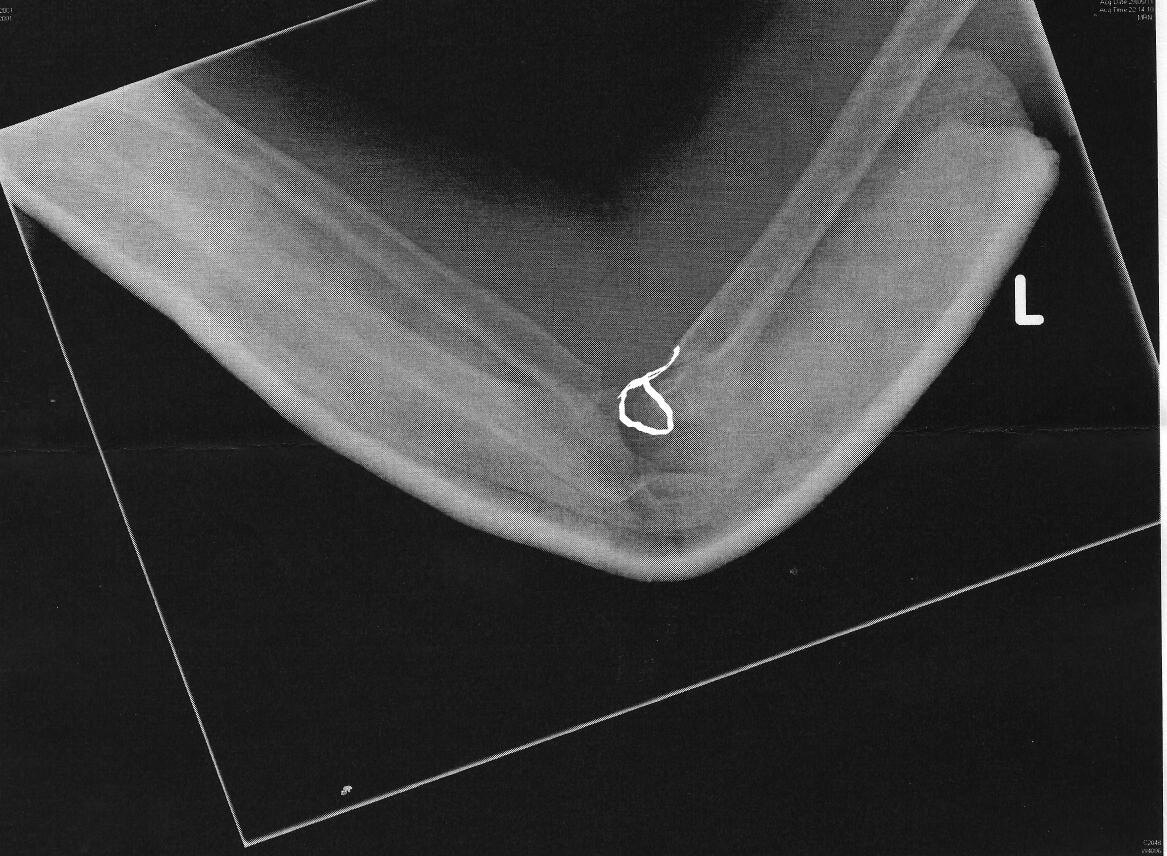

Another 30 minutes later with the help of laugh gas and a pediatric doctor her arm was put in a half cast and another x-ray was taken.

Note: this picture clearly shows the half cast as well as the reset bone structure which is now a lot more brought forward and aligned with the humerus bone.